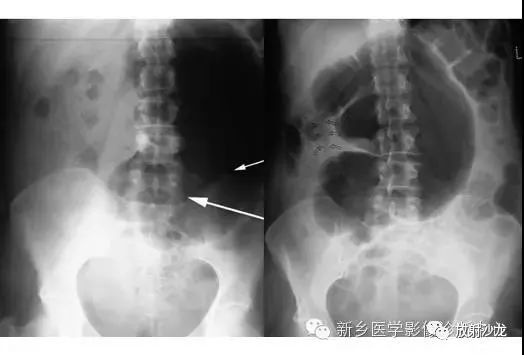

上图符合53岁,女性,肠梗阻所做的腹部平片。发病初所拍图像在左侧,24小时后所拍图像在右侧。是什么原因造成病人梗阻?众多发现都在目前,不要被箭头影响。

该患者存在一个大的盲肠肠扭转。左侧图像显示一个没有任何可见结肠袋(短箭头),内脏充满大量气体。在升结肠(红色箭头)存在粪便与空气,这表明没有完全阻塞并且一些气体正向远端移动。右图像显示内脏位置的变化,这表明梗阻是非固定的。扭转是由弯曲的箭头所圈出。典型的表现为盲肠头朝向右侧髂窝与肠扭转突出向上朝向左上腹部。